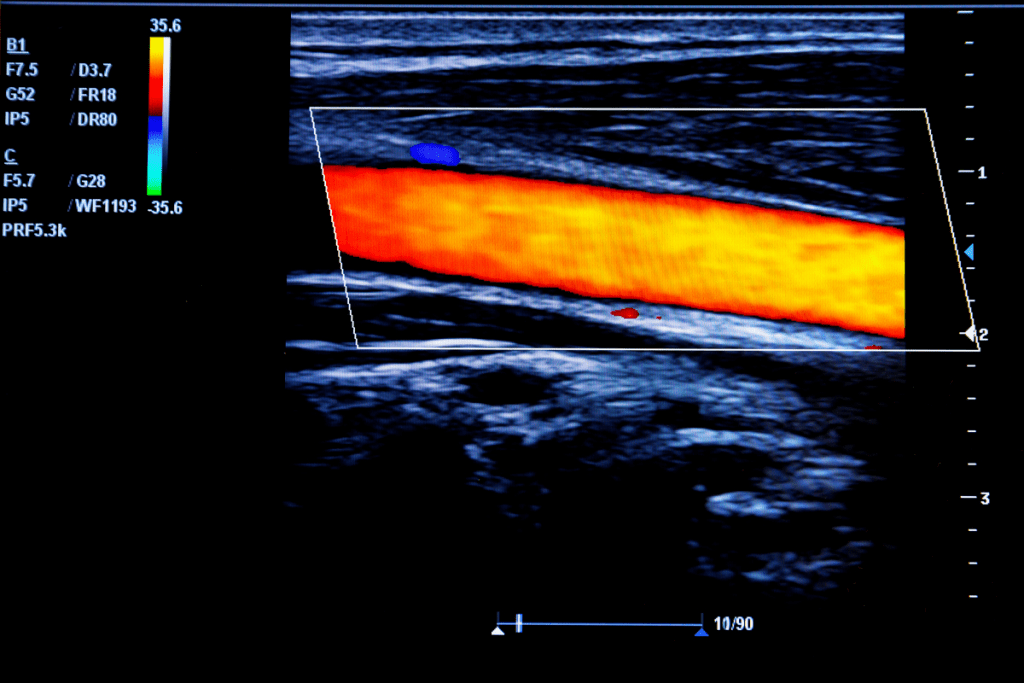

What Do the Colors Mean on an Ultrasound?

Doppler ultrasound uses colors to show blood flow direction and speed. This is key for checking blood vessel health and spotting flow problems.

Basic Color Coding in Doppler Ultrasound

In Doppler ultrasound, colors show blood flow direction and speed. The main idea is to tell blood flow towards or away from the ultrasound machine.

- Towards the transducer: Usually shown as red.

- Away from the transducer: Usually shown as blue.

The color’s brightness also tells us about blood flow speed. Brighter colors mean faster flow, and darker colors mean slower flow.

Red and Blue Color Representation

The red and blue colors on Doppler ultrasound don’t show blood oxygen or cancer. They just show blood flow direction relative to the ultrasound machine.

It’s important to know that color coding can change slightly between machines and settings. But the main idea stays the same: red for flow towards and blue for flow away.

Some key points about red and blue on Doppler ultrasound:

- The colors don’t directly show cancer or benign conditions.

- Abnormal flow might show as a mix of colors.

- Blood flow speed can be guessed from color brightness.

Knowing Doppler ultrasound color coding is key for understanding ultrasound images. While colors are important, they’re just part of a full ultrasound check.

What Red and Blue Actually Indicate

In Doppler ultrasound, red and blue show blood flow direction and speed. Red means flow towards the probe, and blue means flow away. Brighter colors mean faster flow.

The colors on Doppler ultrasound images show more than just pictures. They reveal the direction and speed of blood flow. This technology has changed how doctors diagnose and track vascular issues by showing blood flow visually.

Blood Flow Direction and Velocity

The colors on Doppler ultrasound images mean different things. Red shows blood flowing towards the transducer, and blue shows it flowing away. The color’s brightness shows how fast the blood is moving – the brighter, the faster.

This color system is key for spotting normal and abnormal blood flow. For example, a healthy artery has blood flowing smoothly, shown by a steady color.

Interpreting the Color Spectrum

Understanding Doppler ultrasound colors means knowing about blood flow direction and type. Turbulent or abnormal flow shows up as a mix of colors, hinting at problems like stenosis.

The color’s intensity also tells us about blood flow speed. Faster flows are brighter, slower flows are darker. This helps doctors spot issues like stenosis or thrombosis.